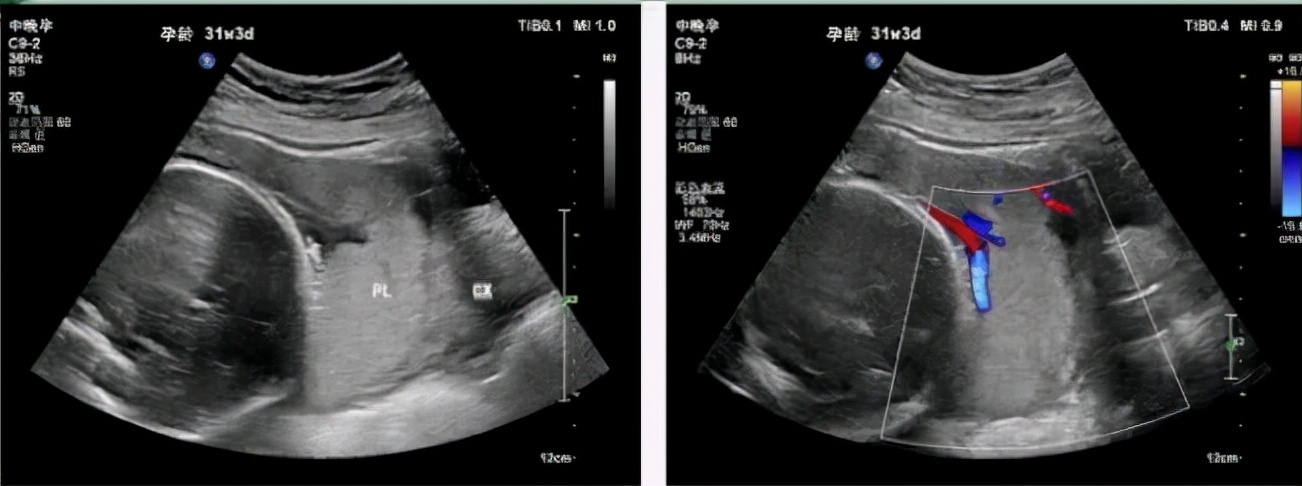

(1) 完全性前置胎盘:指孕28周后胎盘下缘完全覆盖宫颈内口(其中中央性前置胎盘是指胎盘中心部分覆盖在宫颈内口区域),横切面时,宫颈上方全部为胎盘回声。

(2) 部分性前置胎盘:胎盘组织部分覆盖宫颈内口。大多数超声检查前置胎盘时宫颈口尚未开张,而临床分类是在临产宫颈口开至3 cm以上第一次阴道检查时进行,因此不下部分性前置胎盘的超声诊断。

(3) 边缘性前置胎盘:是指孕28周后胎盘下缘达宫颈内口边缘(≤2 cm),但未覆盖宫颈内口。

(4) 低置胎盘(孕28周之前):胎盘下缘距宫颈内口≤2 cm。

(3) 经阴道超声是诊断前置胎盘的较好手段,可以弥补经腹部超声的不足。